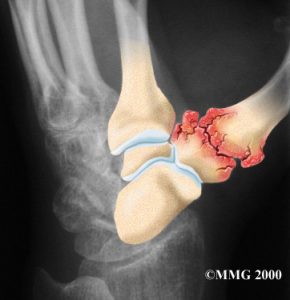

A laxidez ligamentar provoca sub-luxação articular; isto é, o osso metacarpiano, devido à incompetência ligamentar, vai-se deslocar parcialmente em relação ao trapézio; este processo vai desencadear um desgaste rápido da cartilagem.

A sub-luxação vai causar uma saliência da base do polegar.

Com o avançar da artrose surgem osteófitos, tornando a deformidade mais visível.